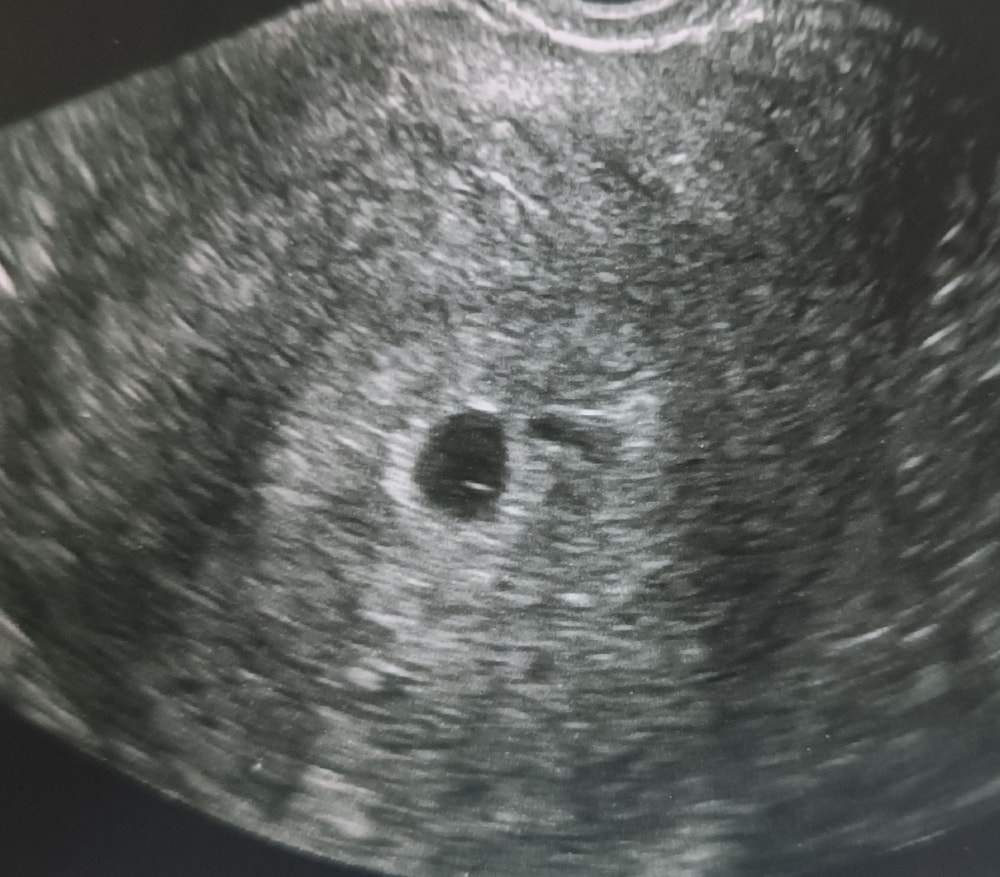

Эмбрион или желточный мешок?

но вопрос, разве может быть уже и желточный мешок и эмбрион? Или все таки пока просто ЖМ? Но то что кто-то сидит внутри яйца я вижу, самое главное что моя бусинка не пустая)

Ничего себе, такое маленькое плодное яйцо и уже видно эмбриончик в 1 мм. Прям очень хороший аппарат, в следующий раз уже сб послушаете

Светлана , нашла свое узи 5+6 недель. Вот тут нет еще эмбриона, но жм есть, врач сказала. Видите, пусто. А у вас прям точка хорошо видна. Наверно у вас это точно эмбрион

На втором снимке чётко виден эмбрион с желточным мешком, это уже не просто ЖМ. Сердцебиение должно скоро появиться, если срок подходит. Всё выглядит хорошо.

Ксюша, а сможете объяснить где вы это видите? Я просто поняла черный круг это яйцо, а внутри точка это ЖМ. Исправьте пожалуйста если не так. Срок по узи 5.2, по М-5,5